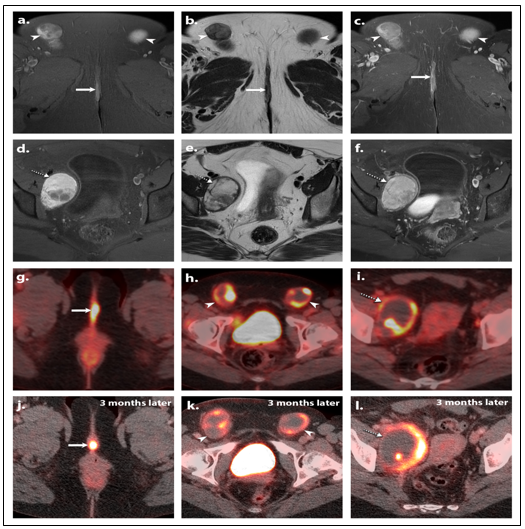

Figure 1: Baseline MRI Axial T1 FS (a and d), Axial T2 (b and e) and Axial T1 FD post contrast (c and f) images show the primary lesion in the right labia (white arrows) and large necrotic bilateral inguinal lymph nodes (white arrowheads) with T1 hyperintense signal, T2 hypointense signal and a heterogeneous post contrast enhancement. Large necrotic right iliac lymph node (dotted white arrow) is also noted with T1 hyperintense signal, and T2 heterogeneous signal with cystic degeneration and a heterogeneous post contrast enhancement.

Axial PET/CT images (g, h, and i) show the vulvar lesion (white arrow) with high maximum standardized uptake value (SUVmax) of 12.2. The necrotic right inguinal (white arrowhead), left inguinal (white arrowhead), and right iliac lymphadenopathy (dotted white arrow) show peripheral hyper metabolism and high SUVmax of 17.1, 14.9, and 12.7 respectively.

3 months later after starting neoadjuvant immunotherapy, axial PET/CT images (j, k and l) show the vulvar lesion (white arrow) with nearly the same SUVmax (12.2). The right inguinal (white arrowhead), left inguinal (white arrowhead), and right iliac lymphadenopathy (dotted white arrow) show slight increase in size and lower SUVmax of 9.6, 7, and 9.9 respectively. The findings were consistent with pseudoprogression/response to therapy.

The images show the vulvar tumor and involvement of the bilateral inguinal, and right external iliac lymph nodes. The patient was started on neoadjuvant immunotherapy ipilimumab and nivolumab.